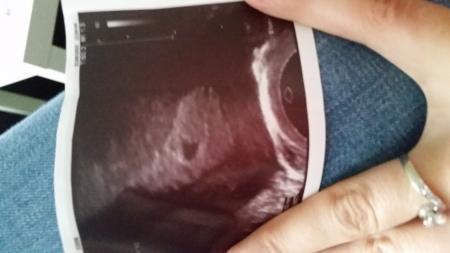

Ich war ja gestern bei der ersten Ultraschall Untersuchung früher wegen dieser bräunlichen schmierblutung. Der Artzt hat die aufgebaute Schleimhaut gesehen und das Fruchtbläschen. Er konnte nicht sehen und sagen warum ich diese Schmierblutung ab und zu habe.ich soll am 11.9. Nochmal kommen und dann müsste mann das Herz schlagen sehen. Und dann würde ich auch den Mutterpass bekommen wenn alles in Ordnung ist. So nun zum eigentlichen Problem. Gestern bin ich nach Hause gekommen und hatte wieder mehr schmierblutung, und am Abend so nen Klumpen so groß wie ne Erdnuss. Heute morgen wieder mehr braun bis dunkelrotes blut. Hatte das jemand ist das in Ordnung weil sich der Körper ja noch einstellt. Was soll ich machen ich war ja gestern bei der Untersuchung. Ich habe Angst.

Hier auch ein kleines Foto